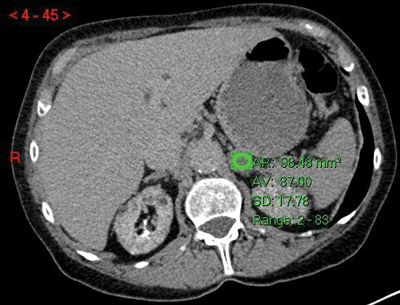

The two most common imaging modalities used to assess indeterminate adrenal lesions are multi-phase IV contrast-enhanced CT scanning and multi-sequence MRI scanning. Radiology departments vary on which method they choose depending on modality preference and capacity. If an adrenal lesion is detected incidentally on a CT scan, then it can often be classified as benign based on this initial scan. Eighty percent of adrenal adenomas have a high level of microscopic (intra-cytoplasmic) fat and will therefore have low Hounsfield units (HU). On an unenhanced CT scan, a lesion with an average HU <10 will have a sensitivity of 71% and a specificity of 98% for adenoma [4] (Figure 2). If the lesion has an average HU of >10 then adrenal-specific imaging will need to be performed to determine whether the lesion is a ‘lipid-poor’ adenoma or whether it is a malignant lesion.

Figure 2: Adenoma on unenhanced CT shown as a well-defined left adrenal nodule with HU <10.